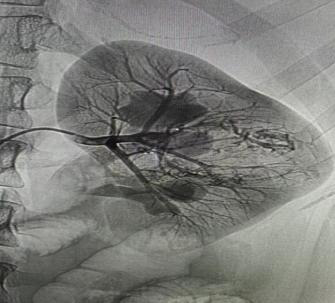

术中通过DSA造影,顺利找到肾脏出血的精准位置,左肾平滑肌脂肪瘤供血动脉破裂出血。通过微导管超选出血责任血管并栓塞出血动脉,有效地阻止了出血。在完成栓塞后,对原出血部位进行了再次的造影检查,发现原本外溢的造影剂已经消失,这表明出血动脉已经被成功封堵。术后患者生命体征平稳,症状较前明显改善,尿液由血红色逐渐恢复清亮。